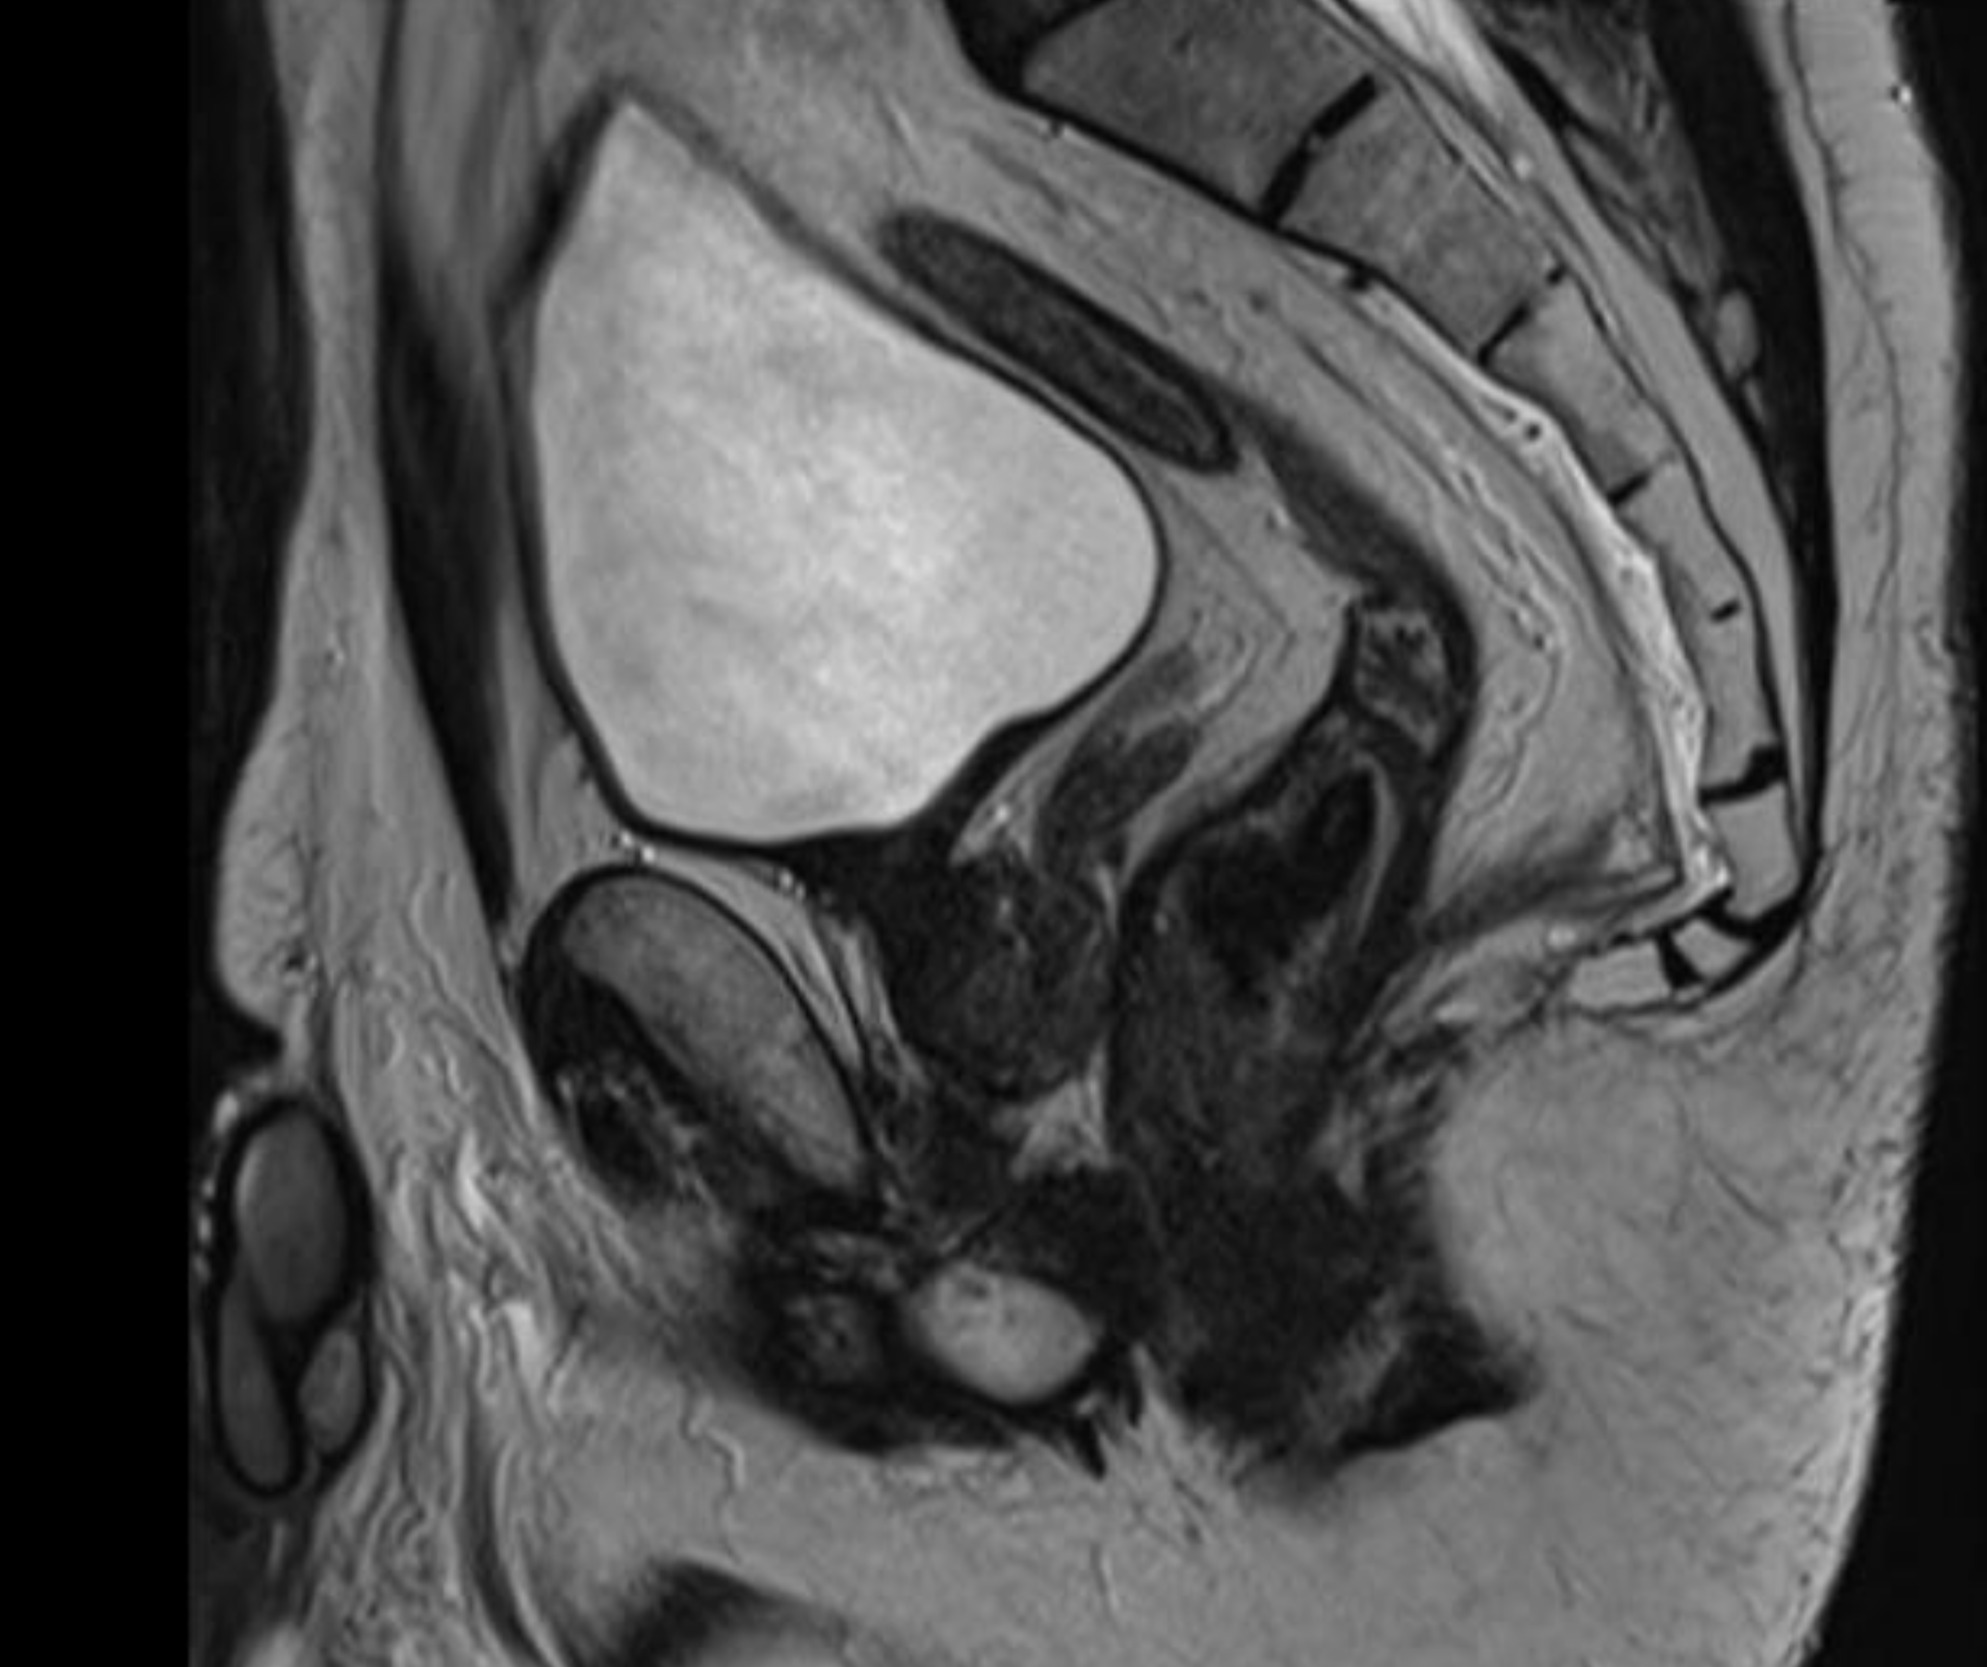

We report the case of a 52-year-old male patient in whom a vegetative lesion of the distal rectum was incidentally identified during urological evaluation for bladder carcinoma. The patient’s medical history was notable for episodes of hematochezia, which had not previously undergone proctological assessment. Endoscopic investigations were conducted (Figure 1); however, biopsy specimens yielded non-diagnostic results. Computed tomography (CT) imaging demonstrated apparent obliteration of the distal rectal lumen by a parietal mass measuring approximately 4 cm. To further characterize the lesion, contrast-enhanced MRI was performed, confirming the presence of an expansive mass in the distal rectum (Figure 2).

Inhomogeneous signal hyperintensity in T2-weighted sequences with a fluid/fluid level appearance, isointensity signal in T1-weighted sequences, no signal reduction in T1-weighted sequences in opposition of phase in agreement with the absence of a lipid component, no signs of signal restriction in diffusion (ADC 1.6), thin peripheral contrast enhancement, and thin septa in the structure were all features of the MRI. The lesion on the right posterolateral side appeared to affect the muscular coat, extending to the serosa raising suspicion for a teratomatous-type lesion. Following multidisciplinary consultation, surgical excision was planned. A transanal local excision was performed under general anesthesia (Figure 3). The patient’s postoperative course was uneventful, and he was discharged on the first postoperative day. Histopathological analysis revealed an edematous, ulcerated, and chronically inflamed segment of the large intestinal wall, containing lymphatic and intraparietal blood vessel ectasias consistent with hemolymphangioma. No postoperative complications were observed. The patient underwent regular follow-up evaluations, including proctological examinations, CT scans, and MRI studies (Figure 4) every six months for the initial two years, followed by annual assessments. At four years postoperatively, there is no evidence of disease recurrence.